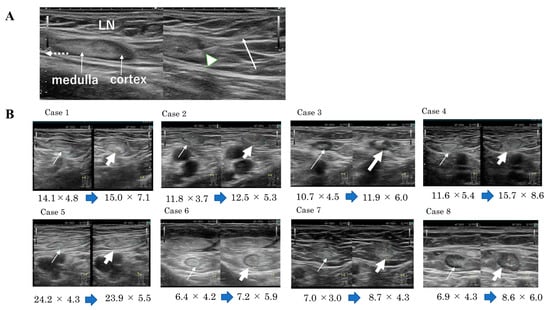

7. Techniques of Intranodal Administration of Mature DCs